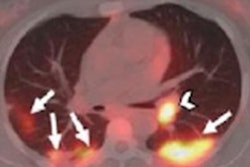

- Prior to surgery, FDG-PET/CT can identify lung cancer patients who may be at higher risk of developing advanced disease.

Finally, as the COVID-19 pandemic continues, molecular imaging is revealing why it is an unmatched modality for diagnosing inflammation and infection. Researchers in New York City drew on imaging performed at the height of the pandemic there to show FDG-PET/CT can predict the severity of COVID-19 infection.